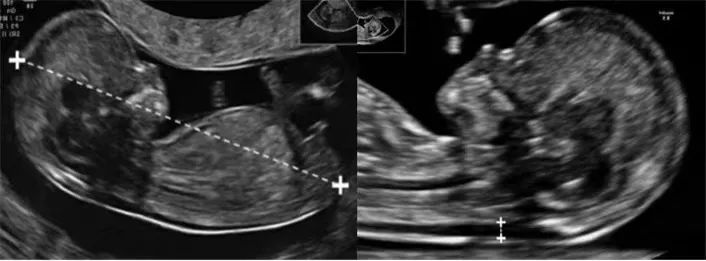

自动化技术可进行胎儿颈项透明层、颅内透明层的精准测量,评估早孕期胎儿染色体异常的风险,并对中孕期开放性脊柱裂的风险进行预测。

盆底三维四维超声有着多平面成像的优势,通过容积数据采集获得更清晰的图像,为临床诊断提供更丰富、有效的信息;妇科肿瘤方面,“煊流技术”提高了微小血管的敏感性,有助于肿瘤良恶性的鉴别诊断。